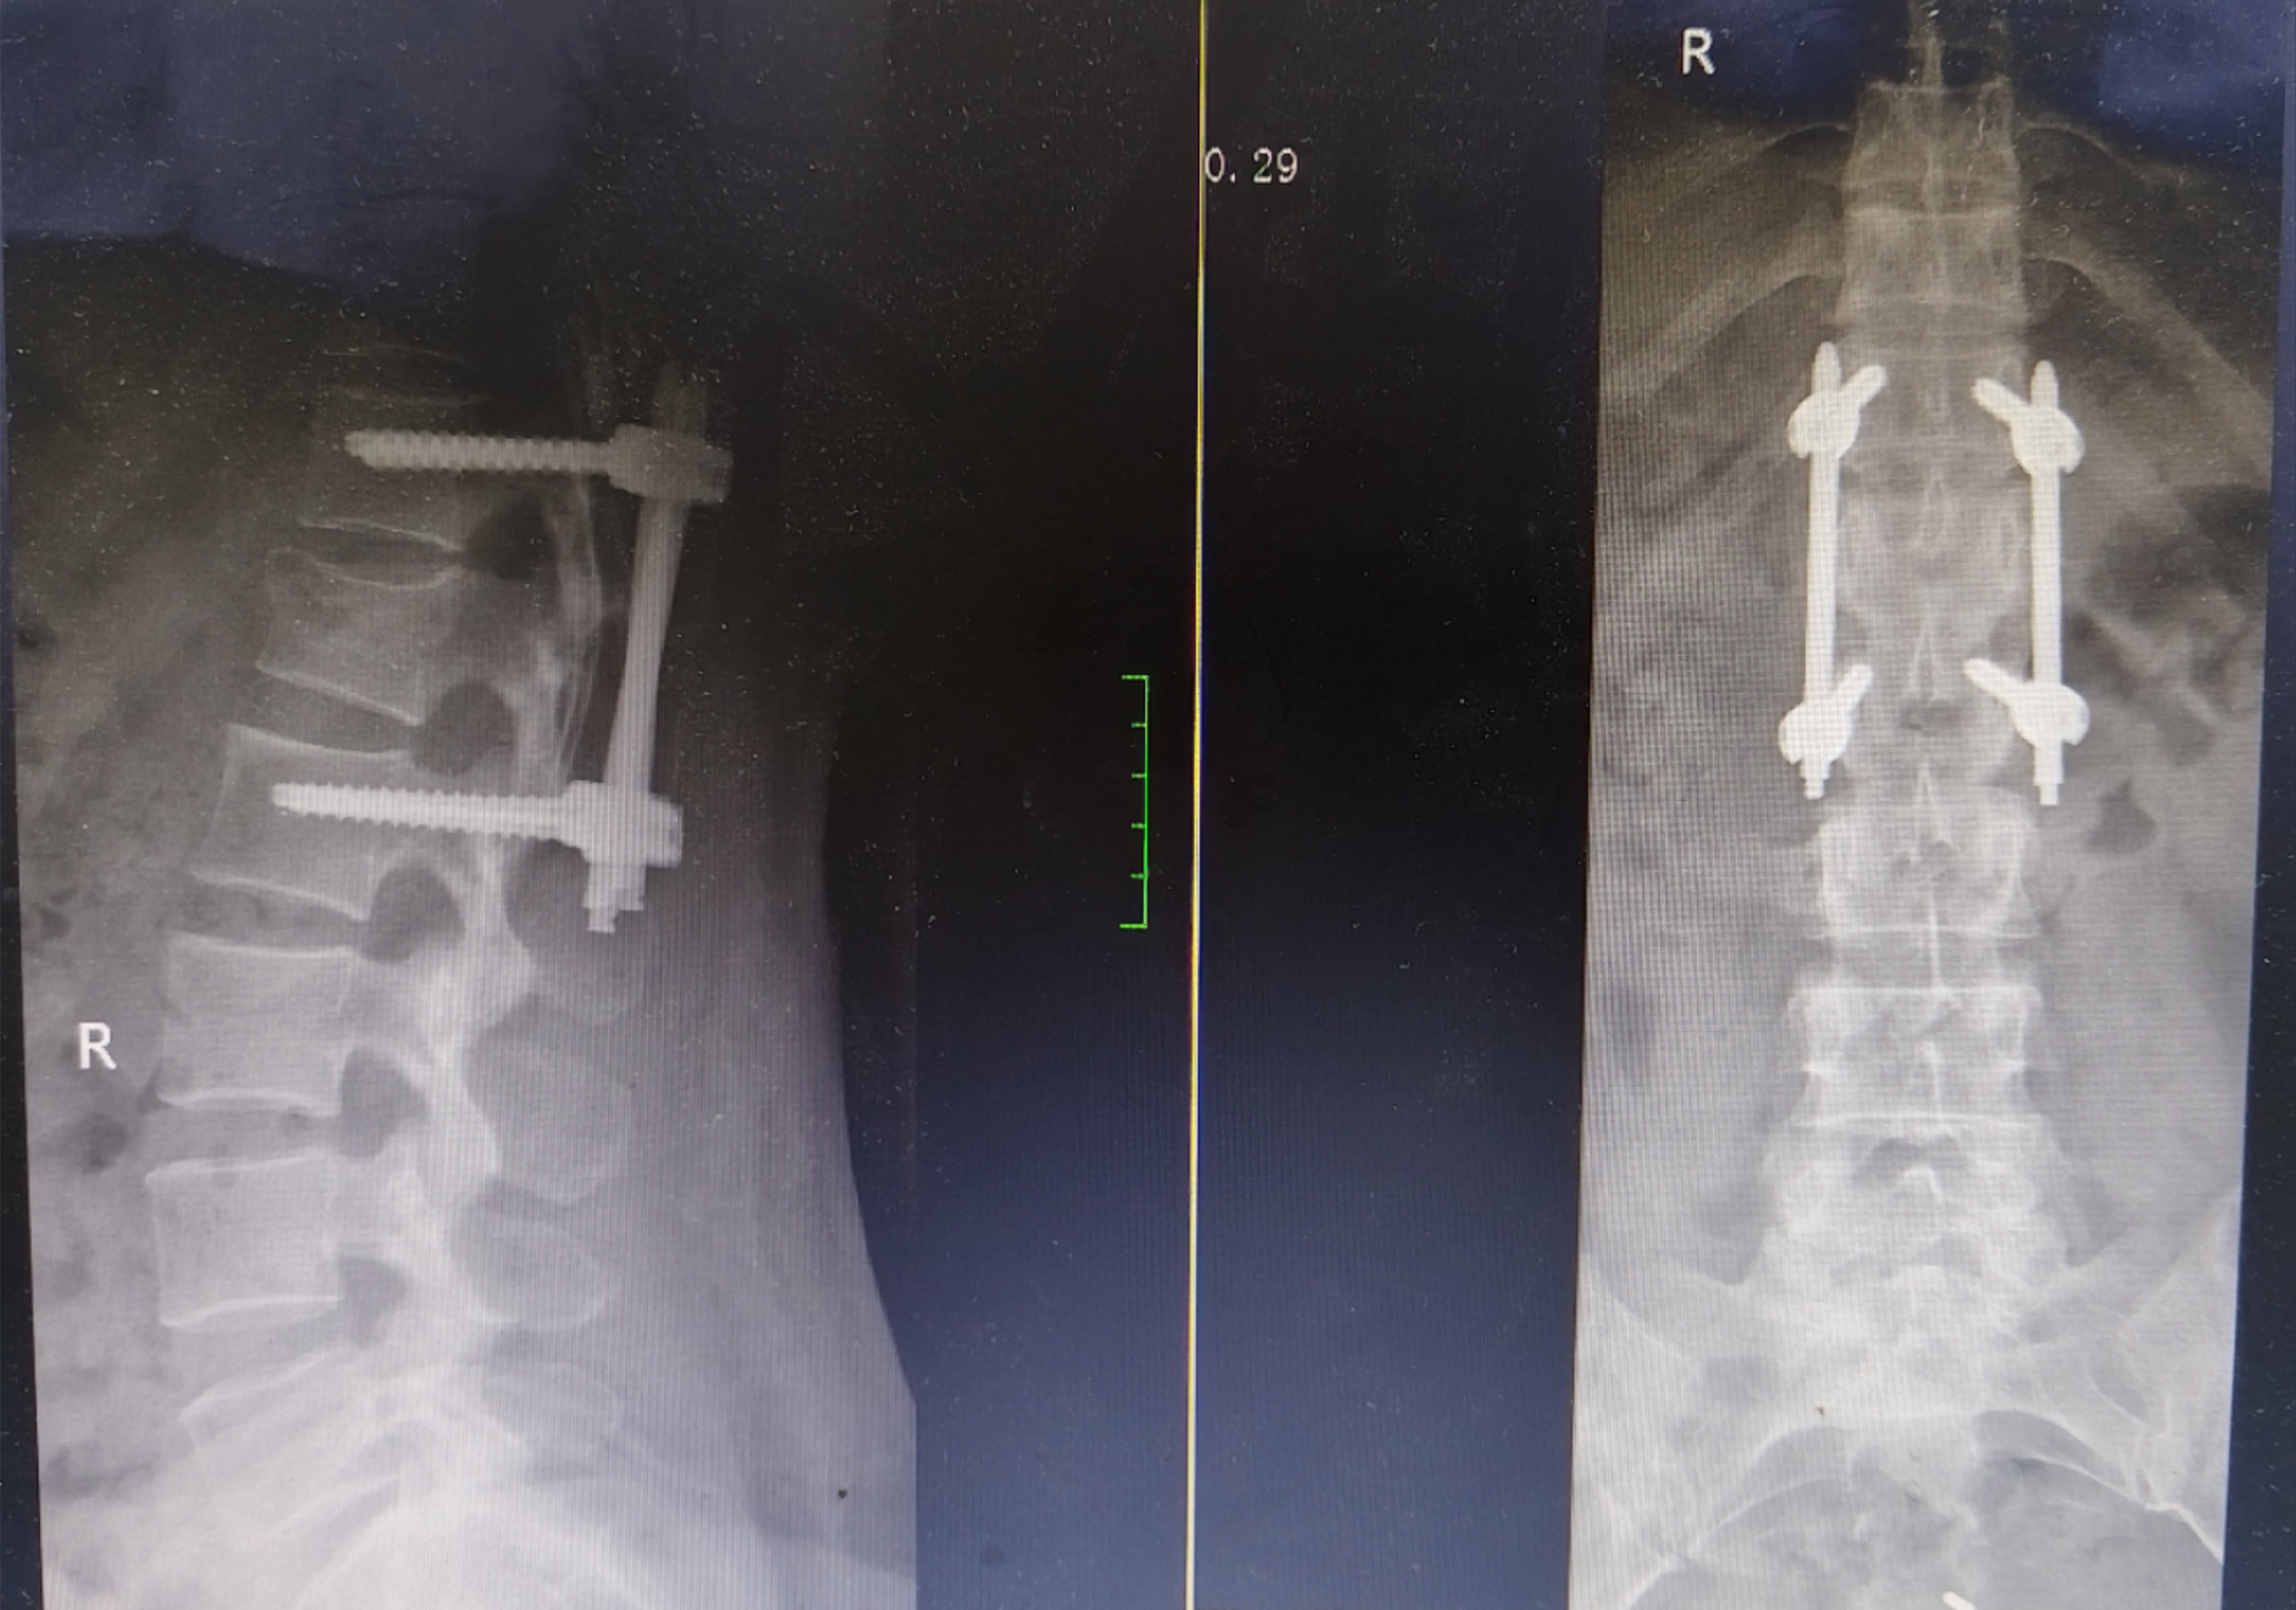

术前检查结果显示王女士腰椎压缩性骨折

术后恢复良好

连续几天的疼痛让王女士饭也吃不下,睡也睡不好,入院时,她已经出现了严重的低钾血症和低蛋白血症。完善术前准备后,骨科团队为王女士实施了微创经皮腰椎内固定手术。术后经过恢复,王女士于昨日顺利出院。